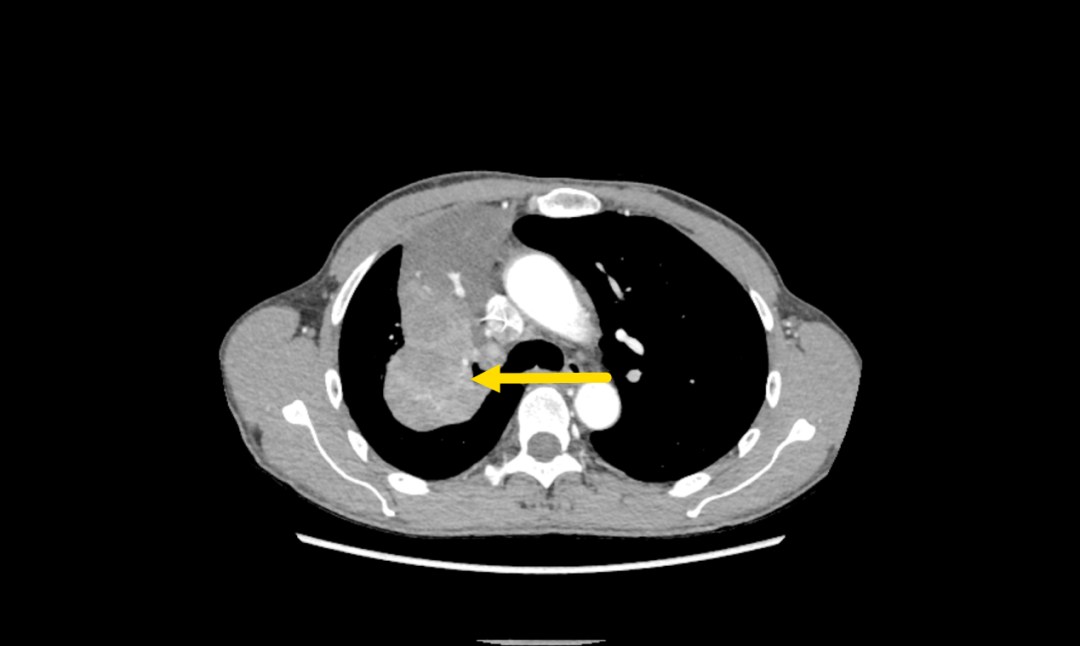

患者,男,57岁,4月余前入院,经CT引导经皮肺穿,病理证实为腺癌,基因检测未发现常见驱动基因突变。患者有吸烟史40余年,每日2包,已戒3月余。患者已经接受了5次的免疫+化疗治疗,最佳疗效为PR(部分缓解),但最近复查肺部CT,提示病情进展。

▲胸部增强CT提示右肺肿块(黄色箭头为肿瘤)

面对复杂的病情,呼吸与危重症医学科学科带头人、省医派驻专家罗少华指出,患者基线肿瘤分期属IIIB期,常规的免疫+化疗方案疗效不佳,存在肿瘤耐药情况,可尝试载药微球支气管动脉化疗栓塞术,以期缩小病灶,为手术创造机会,呼吸介入团队经过缜密的术前讨论和评估,认为患者有BACE适应证。征得患者及家属充分知情同意后,呼吸介入团队成功为患者实施了BACE手术,术后造影显示肿瘤区造影剂滞留,血流速度明显减慢,封堵效果满意,标志着手术取得圆满成功。